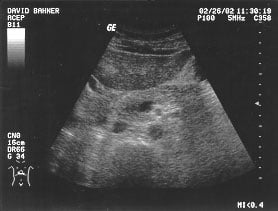

Aorta - suprarenal (unlabeled)